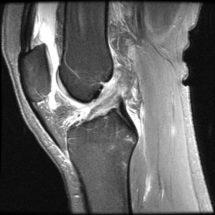

To see pictures of a torn ACL, including before-and-after pictures of ACL reconstruction surgery, please visit our knee arthroscopy gallery.